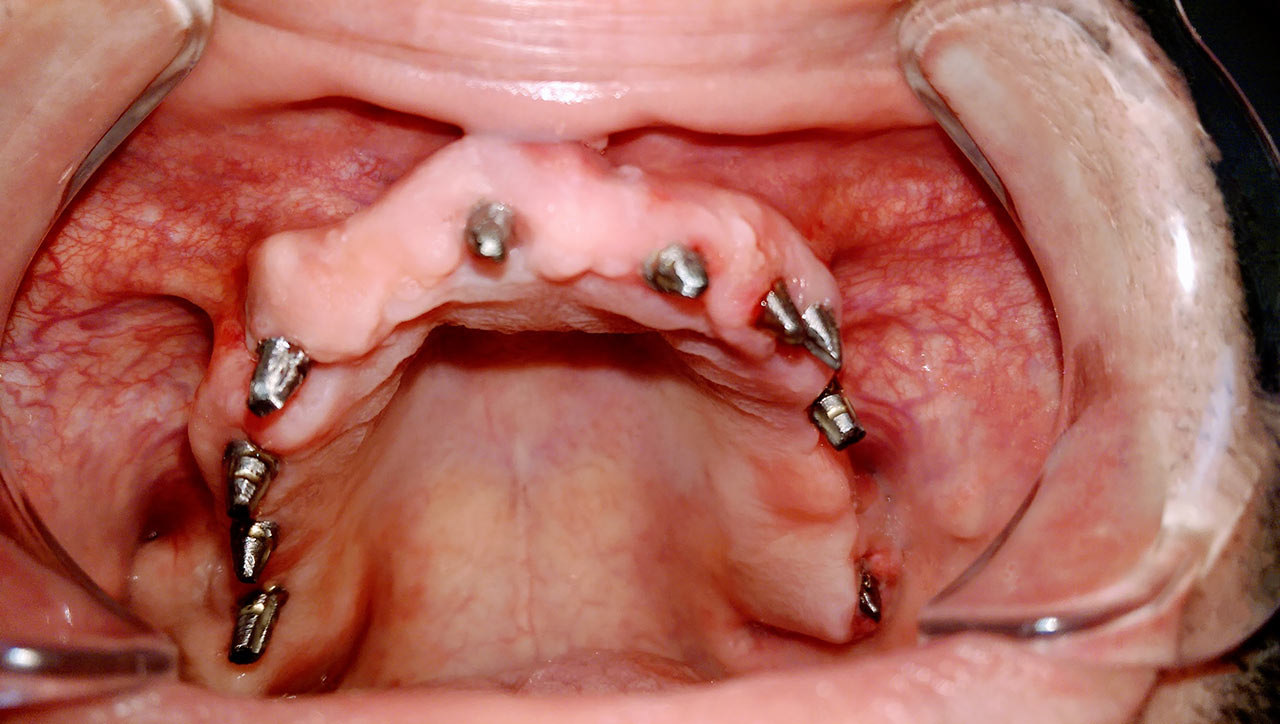

Elhanyagolt fogsor cseréje 2 nap alatt

2 nap alatt varázsoltuk ezt a szép esztétikus alsó, felső körhídat implantátumokkal megtámasztva a korábban elhanyagolt szájba. Az 1. nap 26 fogat távolítottunk el, mert annyira rossz állapotban voltak, és rögtön azonnal terhelhető IHDE svájci implantátumokat raktunk be, fentre 8, lentre 6 darabot. A sebeket összevarrtuk és intraorális szkennerrel digitális lenyomatot vettünk. 2 nap múlva pedig beragasztottuk a kész PMMA műanyag körhidakat. Dr. Kelemen Péter és a Symbion Fogtechnika munkája.